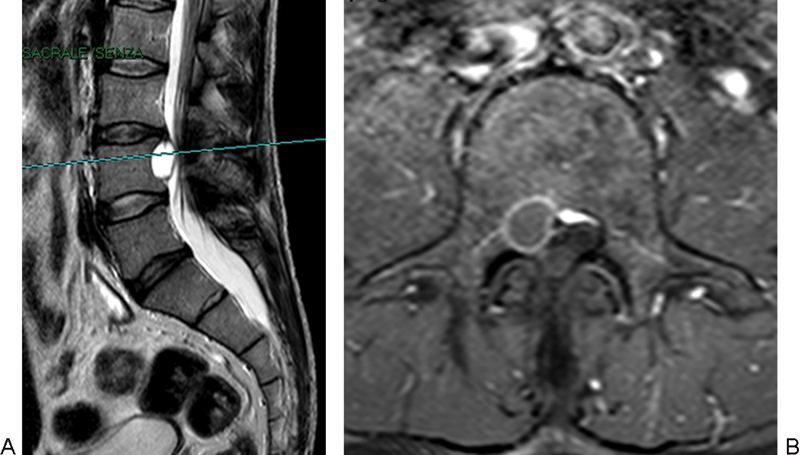

研究设计、个案报告及文献回顾。目的报告一例成功应用显微手术治疗腰椎间盘囊肿的病例,并对目前有关腰椎间盘囊肿诊断和治疗的文献进行综述。方法男性患者,43岁,表现为严重的背部疼痛,放射至右腿,并伴有右侧L3和L4皮节的感觉异常。腰椎磁共振成像显示在L3-L4椎间盘水平有椎管内、硬膜外占位性病变,导致神经结构受压。手术切除病变,诊断为腰椎间盘囊肿。术后症状改善,无并发症出院。对截至2014年2月发表的相关文章进行系统综述。检索关键文章以确定描述腰椎间盘囊肿的诊断和治疗方式以及显微手术与内窥镜治疗的有效性和安全性的研究。结论腰椎间盘囊肿是引起腰痛和神经根病的罕见原因。报告的病例很少;然而,关于它们的自然历史的结论性信息是不可获得的,最好的治疗方式仍然存在争议。我们认为腰椎间盘囊肿具有特殊的放射学和解剖学特征,应在腰痛和神经根病的罕见病因中进行鉴别诊断。

Study Design Case Report and review of the literature. Objective The objective of the article is to report an illustrative case successfully treated by microsurgery and to review the literature on the current evidence on diagnosis and management of lumbar discal cysts. Methods A 43-year-old male patient presented with severe back pain, radiating down to the right leg, as well as with paraesthesias in the right L3 and L4 dermatomes. Magnetic resonance imaging of the lumbar spine revealed an intraspinal, extradural space-occupying lesion at the L3-L4 disc level, causing compression of the neural structures. The lesion was surgically removed and a diagnosis of lumbar discal cyst was made. Postoperatively, symptoms improved and the patient was discharged with no complications. A systematic review of pertinent articles published up to February 2014 was performed. Key articles were searched to identify studies describing the diagnosis and management modalities of lumbar discal cysts and the comparative effectiveness and safety of microsurgery versus endoscopic treatment. Conclusions Discal cysts are rare causes of low back pain and radiculopathy. Few cases have been reported; however, conclusive information about their natural history is not available and the best mode of treatment remains controversial. We submit that lumbar intervertebral disc cysts, with their peculiar radiological and anatomic features, should be considered in the differential diagnosis among rare causes of low back pain and radiculopathy.